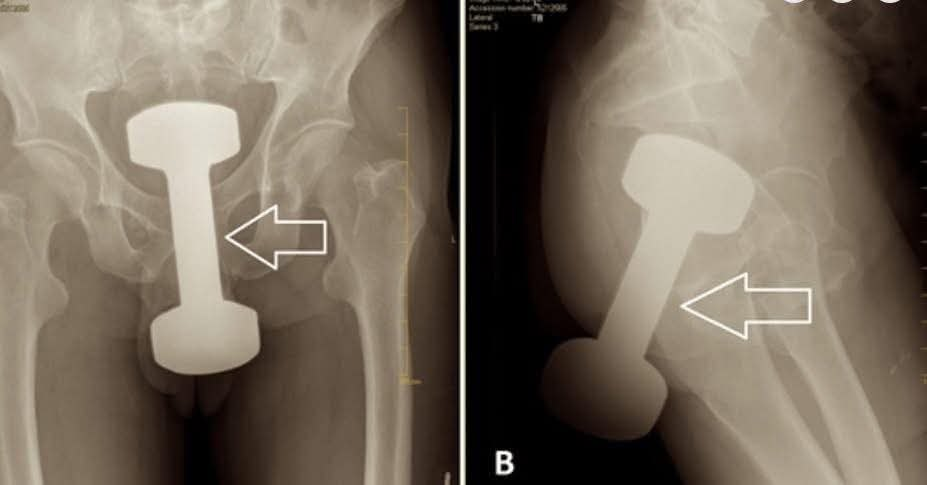

Imagine the shock when a patient arrived at the emergency room in unbearable pain, unable to walk, sit, or even speak properly — and the X-ray revealed the cause: a 5-pound dumbbell lodged deep inside his rectum. This wasn’t a bizarre Photoshop prank or an urban myth; it was a real medical emergency that pushed doctors to their limits. The human body is simply not designed to accommodate such a heavy object in such a delicate place, and the situation was nothing short of a “final boss” case in the realm of unusual ER admissions.

Doctors have seen their fair share of strange objects before — from cables and candles to lightbulbs and spray cans — but a dumbbell of that size and weight was exceptional. The removal required a complex surgical procedure, not simply pulling it out the way it entered, but through invasive abdominal surgery due to the risks involved: internal bleeding, swelling, and potential rupture of the intestines. The operation demanded a full surgical team and meticulous care to prevent further injury. Following the surgery, the patient was also required to undergo psychiatric counseling, a crucial step considering the psychological factors often behind such cases.

This specific case of a 5-pound dumbbell was documented in a medical journal in 2018, highlighting the challenges medical professionals face in managing these emergencies. It serves as a stark reminder of the complex interplay between physical health and mental wellbeing, and the extraordinary lengths doctors go to save patients from harm — no matter how unusual the situation.